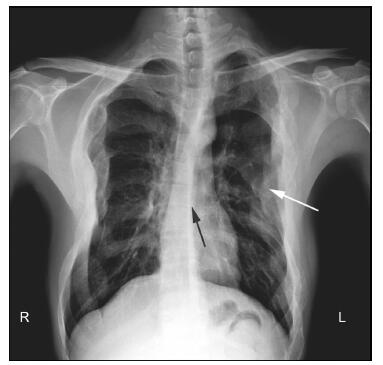

20161117200955  Figure 2 X-ray chest analysis demonstrating scoliosis (black arrow) and multiple local enlargements of the ribs (white arrow).